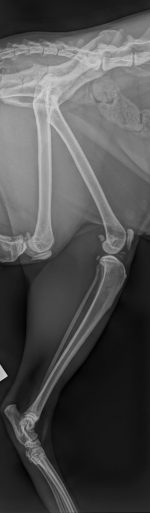

Labrador Retriever de 1 año que acude a consulta para descartar displasia de cadera. Los tutores refieren que “corre como un conejo” y se fatiga rápido durante el juego. No presenta antecedentes relevantes y la exploración física es normal. En la exploración ortopédica se evidencia molestia a la manipulación de la cadera, pese a tener buen rango de movimiento y signo de Ortolani positivo. Se obtiene la radiografía adjunta (Figura 3).

Pregunta: ¿Cuáles son las características clínicas iniciales y los signos radiológicos tempranos que debemos buscar en un perro joven con sospecha de displasia de cadera?

Clínicamente, los signos tempranos incluyen marcha en “salto de conejo”, intolerancia al ejercicio acompañado de atrofia muscular y molestia/dolor a la manipulación. Radiológicamente, los hallazgos iniciales pueden ser sutiles: subluxación leve, cobertura acetabular insuficiente, aumento del espacio articular, cuello femoral algo aplanado y borde acetabular dorsal reducido. En fases muy tempranas puede no haber cambios degenerativos evidentes, pero la relación cabeza–acetábulo puede mostrar laxitud que es clave en el diagnóstico precoz.